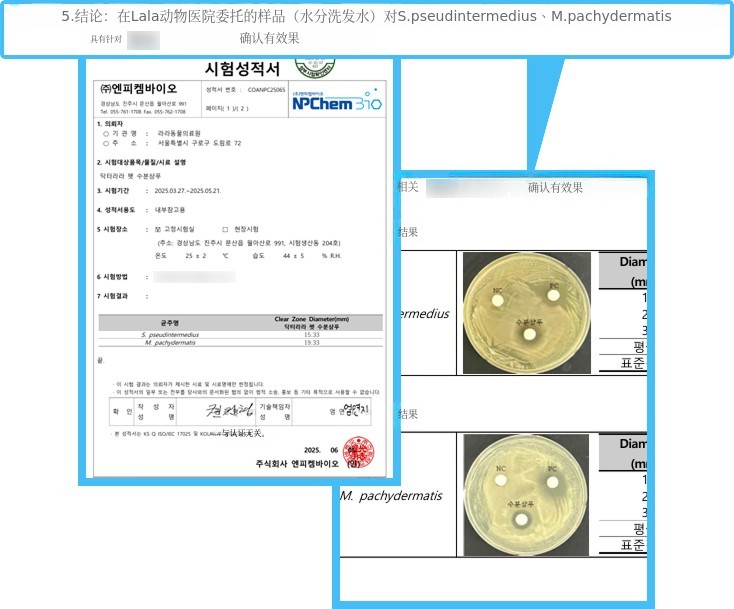

✅金黄色葡萄球菌/大肠杆菌 99.99%!

✅对球菌/马拉色菌同样有效!

- 球菌、马拉色菌认证书 -

- 球菌、马拉色菌认证书 -